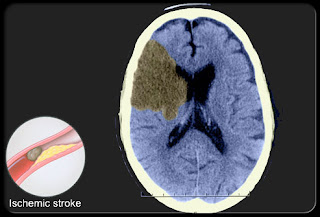

Their are two types of strokes.

1 Hemorrhagic stroke-This stroke caused by a ruptured bleeding artery in the brain.This type of strokes are less common.

2 Ischemic strokes-This occurs due to blockage of blood clot in brain ,which stops the flow of blood.A clot usually forms as a result of fatty plaque buildup that narrow arteries near or in the brain and impedes circulation .A clot may also form in another part of the body,travel, and lodge in a blood vessel that nourishes the brain .